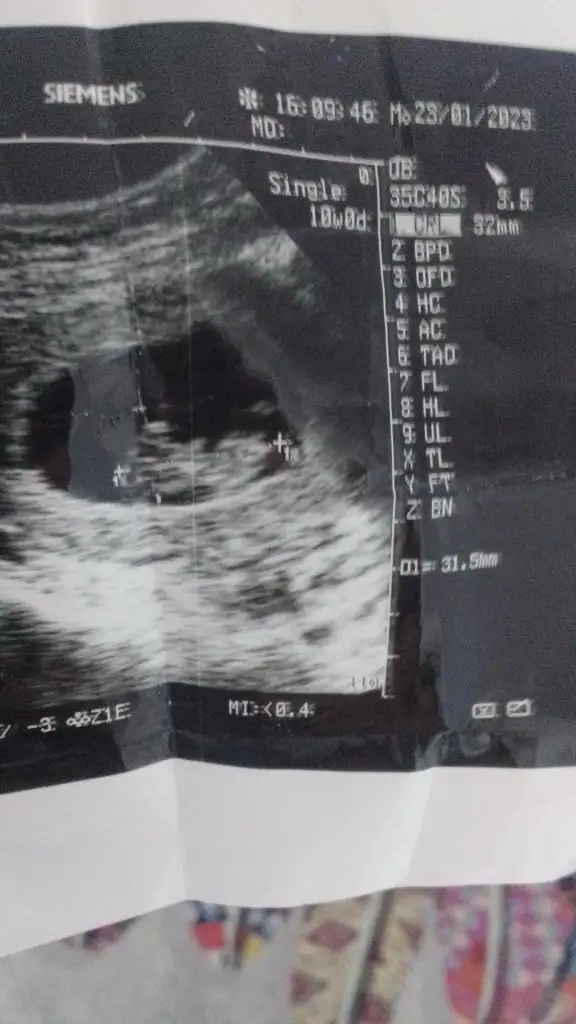

Benimkine bi tahmin edermisiniz 9+2 haftalikSenin erekek

Kız gibi ya sankiBenimkine bi tahmin edermisiniz 9+2 haftalik

Ya bana da bakar mısınız 9 haftalık çok merak ediyorum neye göre anliyosunuz :)Merhabaaşuan 10 haftalık çok erken biliyorum sadece sormak istedim cinsiyet tahmin edebilir misiniizz şimdiden teşekkür ederiimm